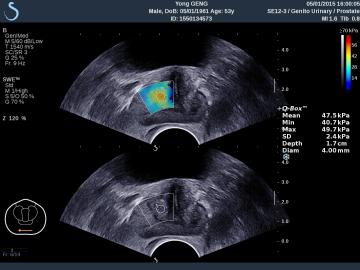

E成像(SWE)實時剪切波彈性成像技術(shù)

“聲藍”獨有的E成像(SWE)實時剪切波彈性成像技術(shù)可以廣泛應(yīng)用在實性臟器腫瘤的早期檢出和鑒別診斷、定量評估、介入穿刺引導(dǎo)、各類疾病治療前后的評價等,也是唯一全面通過美國FDA認證的實時、全幅、全定量的組織硬度可視化測量模式,因而為臨床診斷和治療,提供了安全、無創(chuàng)、有效的最新影像學全新檢查方法。目前已被應(yīng)用于甲狀腺、乳腺、肝臟、腎臟、前列腺、腸管、淋巴結(jié)、肌肉骨骼、軟組織等全身器官的鑒別診斷和定量評估。

彈性超聲與以往普超聲相比,相當于“深觸診”,可以更加直觀地“接觸到”軟組織的形態(tài),并且速度可達到1厘米/秒。與此同時,它的畫面是連續(xù)性的,具有以往單點式的超聲設(shè)備無可比擬的優(yōu)勢。它的“彈性”級別也是最高的,特別適應(yīng)于甲狀腺和乳腺的超聲診斷,并且配備了多個探頭,適用于人體不同部位的超聲需求。彈性超聲的引進與應(yīng)用,可對腫瘤的良惡性鑒別診斷及肝纖維化的無創(chuàng)診斷提供重要依據(jù),可明顯提高診斷準確率,具有非常高的敏感性、特異性,提高檢出率,為臨床診斷及治療提供重要依據(jù),盡早為患者爭取最佳的治療時機。